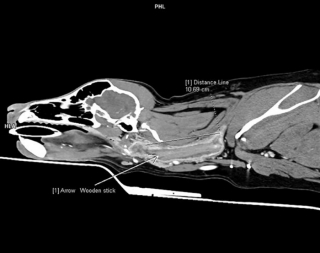

Un bout de bois de 10 centimètres coincé dans la gorge

La chirurgienne vétérinaire découvrira grâce à un scanner que Poppy avait un bout de bois coincé depuis 6 semaines dans la gorge… La chienne avait besoin d’une prise en charge de toute urgence, et a été opérée dans la foulée pour ôter ce fameux bâton. Elle a pu rentrer chez elle tout en suivant un traitement antibiotique pour que son oedème se résorbe correctement.